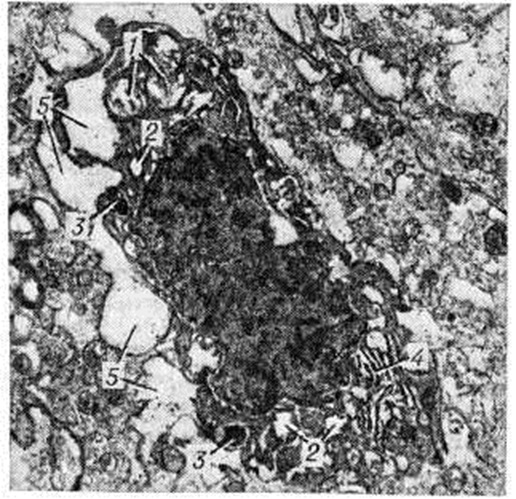

Рис. 1.

Электронограмма нейроцита коры больших полушарий головного мозга. Выражены явления хроматолиза: 1 — набухшие, лишённые крист митохондрии указывают на внутриклеточный отёк и являются ранним признаком гипоксии; 2— осмиофильные включения, свидетельствующие о нарушении липидно-белкового обмена и являющиеся признаком гипоксии; 3 — вакуоли, чаще образующиеся на месте митохондрий, являются следствием гипоксии; 4 — скопление глыбок хроматина в ядре; × 6 300.

В клетках головного мозга обнаруживают вакуолизацию, хроматолиз, гиперхроматоз, кристаллические включения, пикноз, острое набухание, ишемическое и гомогенизирующее состояние нейронов, клетки-тени. При хроматолизе наблюдается резкое уменьшение числа рибосом и элементов гранулярного и агранулярного ретикулума, количество вакуолей увеличивается (рисунок 1). При резком повышении осмиофилии ядра и цитоплазмы митохондрий резко изменяются, появляются многочисленные вакуоли и тёмные осмиофильные тела, цистерны гранулярного ретикулума расширены (рисунок 2).